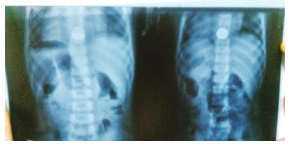

X光片清楚顯示硬幣卡住了浩浩(化名)的喉嚨。 圖/長沙市第三醫(yī)院

小孩名叫浩浩(化名),今年三歲,瀏陽人。16日中午在家玩時,浩浩不知在哪找到一枚一角硬幣,玩了一會兒,小家伙想試試硬幣的味道,結(jié)果不小心把硬幣吞了下去。直到晚飯前,浩浩才告訴父母自己喉嚨里卡了東西。

浩浩父母連夜帶著他來到了長沙市第三醫(yī)院,經(jīng)過手術(shù)后,醫(yī)生從孩子胃里取出一個直徑約2cm的硬幣。